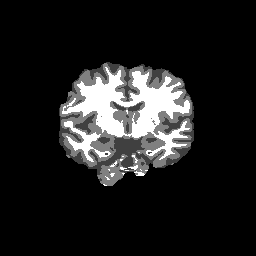

Accuracy is reported as Dice overlaps between a tool's segmentation and the Internet Brain Segmentation Repository (IBSR) manual segmentation for each of the 18 IBSR subjects. The inter-tool comparison (on the left below) shows the median Dice coefficient for each tissue class. The overlaps for FSL (from which the median values are drawn) are shown in the plot on the right.

Overlap coefficients for each tissue class are shown here for each IBSR subject. Select a subject below to see the FSL results compared to other tools.